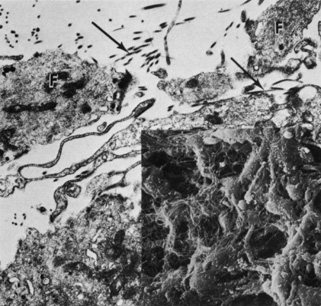

Fibroblasts are prominent on the iris surface. Transmission electron microscopic examination of these fibroblasts reveals abundant mitochondria, rough endoplasmic reticula, free ribosomes, and bundles of filaments (Fig. 9). Some fibroblasts have basal bodies in their cytoplasm, with associated cilia projecting into the anterior chamber (Figs. 10 and 11). Melanocytes are most often found just beneath fibroblasts and contain mitochondria, smooth and rough endoplasmic reticula, free ribosomes, and melanin granules in various stages of development (Fig. 12). The blood vessels and nerve fibers of the anterior border layer are similar to those in the deeper stroma and are discussed later.29

Fig. 9. The anterior border of the iris is composed of a discontinuous layer of fibroblasts (F) and interspersed collagen fibrils (arrows) (×13,800). Inset shows fibroblasts and a meshwork of collagen connecting fibroblasts (×40,500).